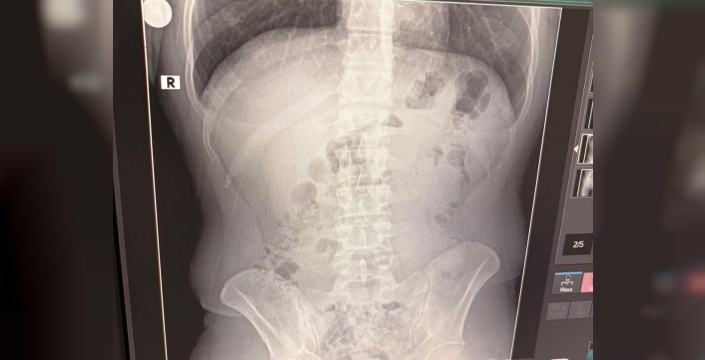

Şüphelilerin bulundukları adreste yapılan arama sırasında, bir şüphelinin üzerinde 1 adet kapsül bulundu. Bu durum üzerine tüm şüpheliler hastaneye sevk edildi. Yapılan röntgen kontrollerinde, 3 kişinin midelerinde kapsüller halinde metamfetamin gizlendiği tespit edildi. Tedavi altına alınan şüphelilerin vücutlarından çıkarılan kapsüller ve evde ele geçirilen maddelerle birlikte toplam 1 kilo 516 gram metamfetamin ele geçirildi. Ele geçirilen uyuşturucu maddelere el konulurken, gözaltına alınan Y.T., A.T. ve M.J. isimli şüpheliler, emniyetteki işlemlerinin ardından adliyeye sevk edildi. Mahkemeye çıkarılan şüpheliler, tutuklanarak cezaevine gönderildi.